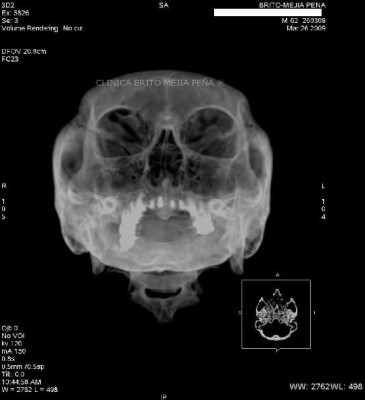

Fractura malar